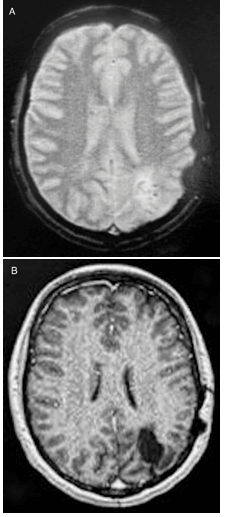

Early postoperative CT and late postoperative MR (36 months) confirmed complete lesion resection (Figure 5). The patient has been followed-up for 3 years, presenting, so far, a good outcome. A recent electroencephalogram was normal. She remains seizure-free since surgery and the anticonvulsant therapy (carbamazepine) was progressively discontinued.

Figure 5: A) Postoperative T2* and B) post contrast T1-weighted brain MR sequences showing complete resection of the lesion.